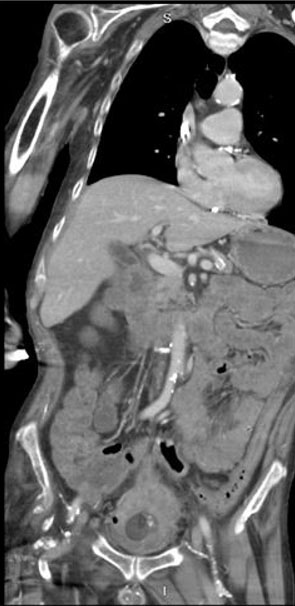

A 62-year-old male with non-oliguric ESRD on hemodialysis along with an indwelling Foley catheter secondary to urinary retention presented to the emergency department (ED) with several days of poor appetite, fever, and decreased output from his urinary catheter. Initial laboratory tests showed leukocytosis with a white blood cell count of 27,000/µL and a fever of 99.5 °F. The Foley was removed, with a significant amount of debris noted at the tip, indicating that it had been clogged. ED nursing staff catheter were unable to replace the catheter. Computed tomography (CT) of the abdomen/pelvis revealed peri-vesical stranding, bladder calculi, and multiple low-attenuation areas within an irregularly thickened bladder wall, suggesting intramural abscesses (Figure 1). No air was noted in the bladder wall or lumen.

Figure 1: Initial CT scan concerning for bladder abscesses. Note the multiple low attenuation fluid collections within the bladder wall circumferentially that do not appear to connect to the lumen of the bladder.